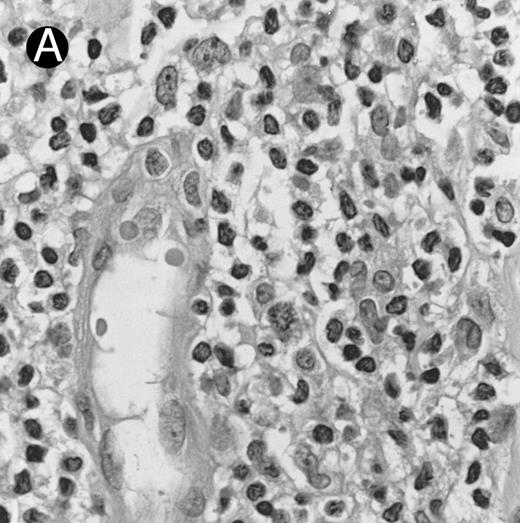

Blastoid NK cell lymphoma (case no. 40). (A) Biopsy shows a diffuse lymphomatous infiltrate with a prominent single-file pattern. (B) The neoplastic cells are medium-sized and possess fine chromatin. Mitotic figures are seen. There is remarkable resemblance to myeloid leukemic infiltration.

Blastoid NK cell lymphoma (n = 2).One patient presented with systemic disease, whereas 1 had localized disease at presentation. Histologically, the infiltrate was diffuse, with a prominent single-file pattern reminiscent of leukemia (Fig 8A). The neoplastic cells were medium-sized and had irregularly folded delicate nuclear membranes, fine chromatin, and tiny nucleoli (Fig 8B). Mitotic figures were easily identified.